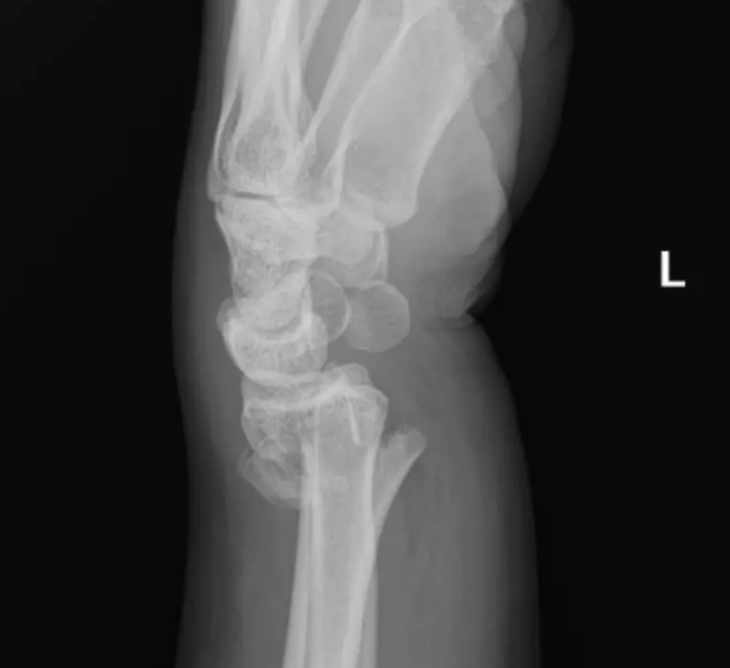

Barton’s Fracture | Intra-articular shear fracture of the dorsal (dorsal Barton’s) or volar (volar Barton’s) rim. The radiocarpal joint subluxes with the fragment — inherently unstable and almost always requires surgical fixation. |